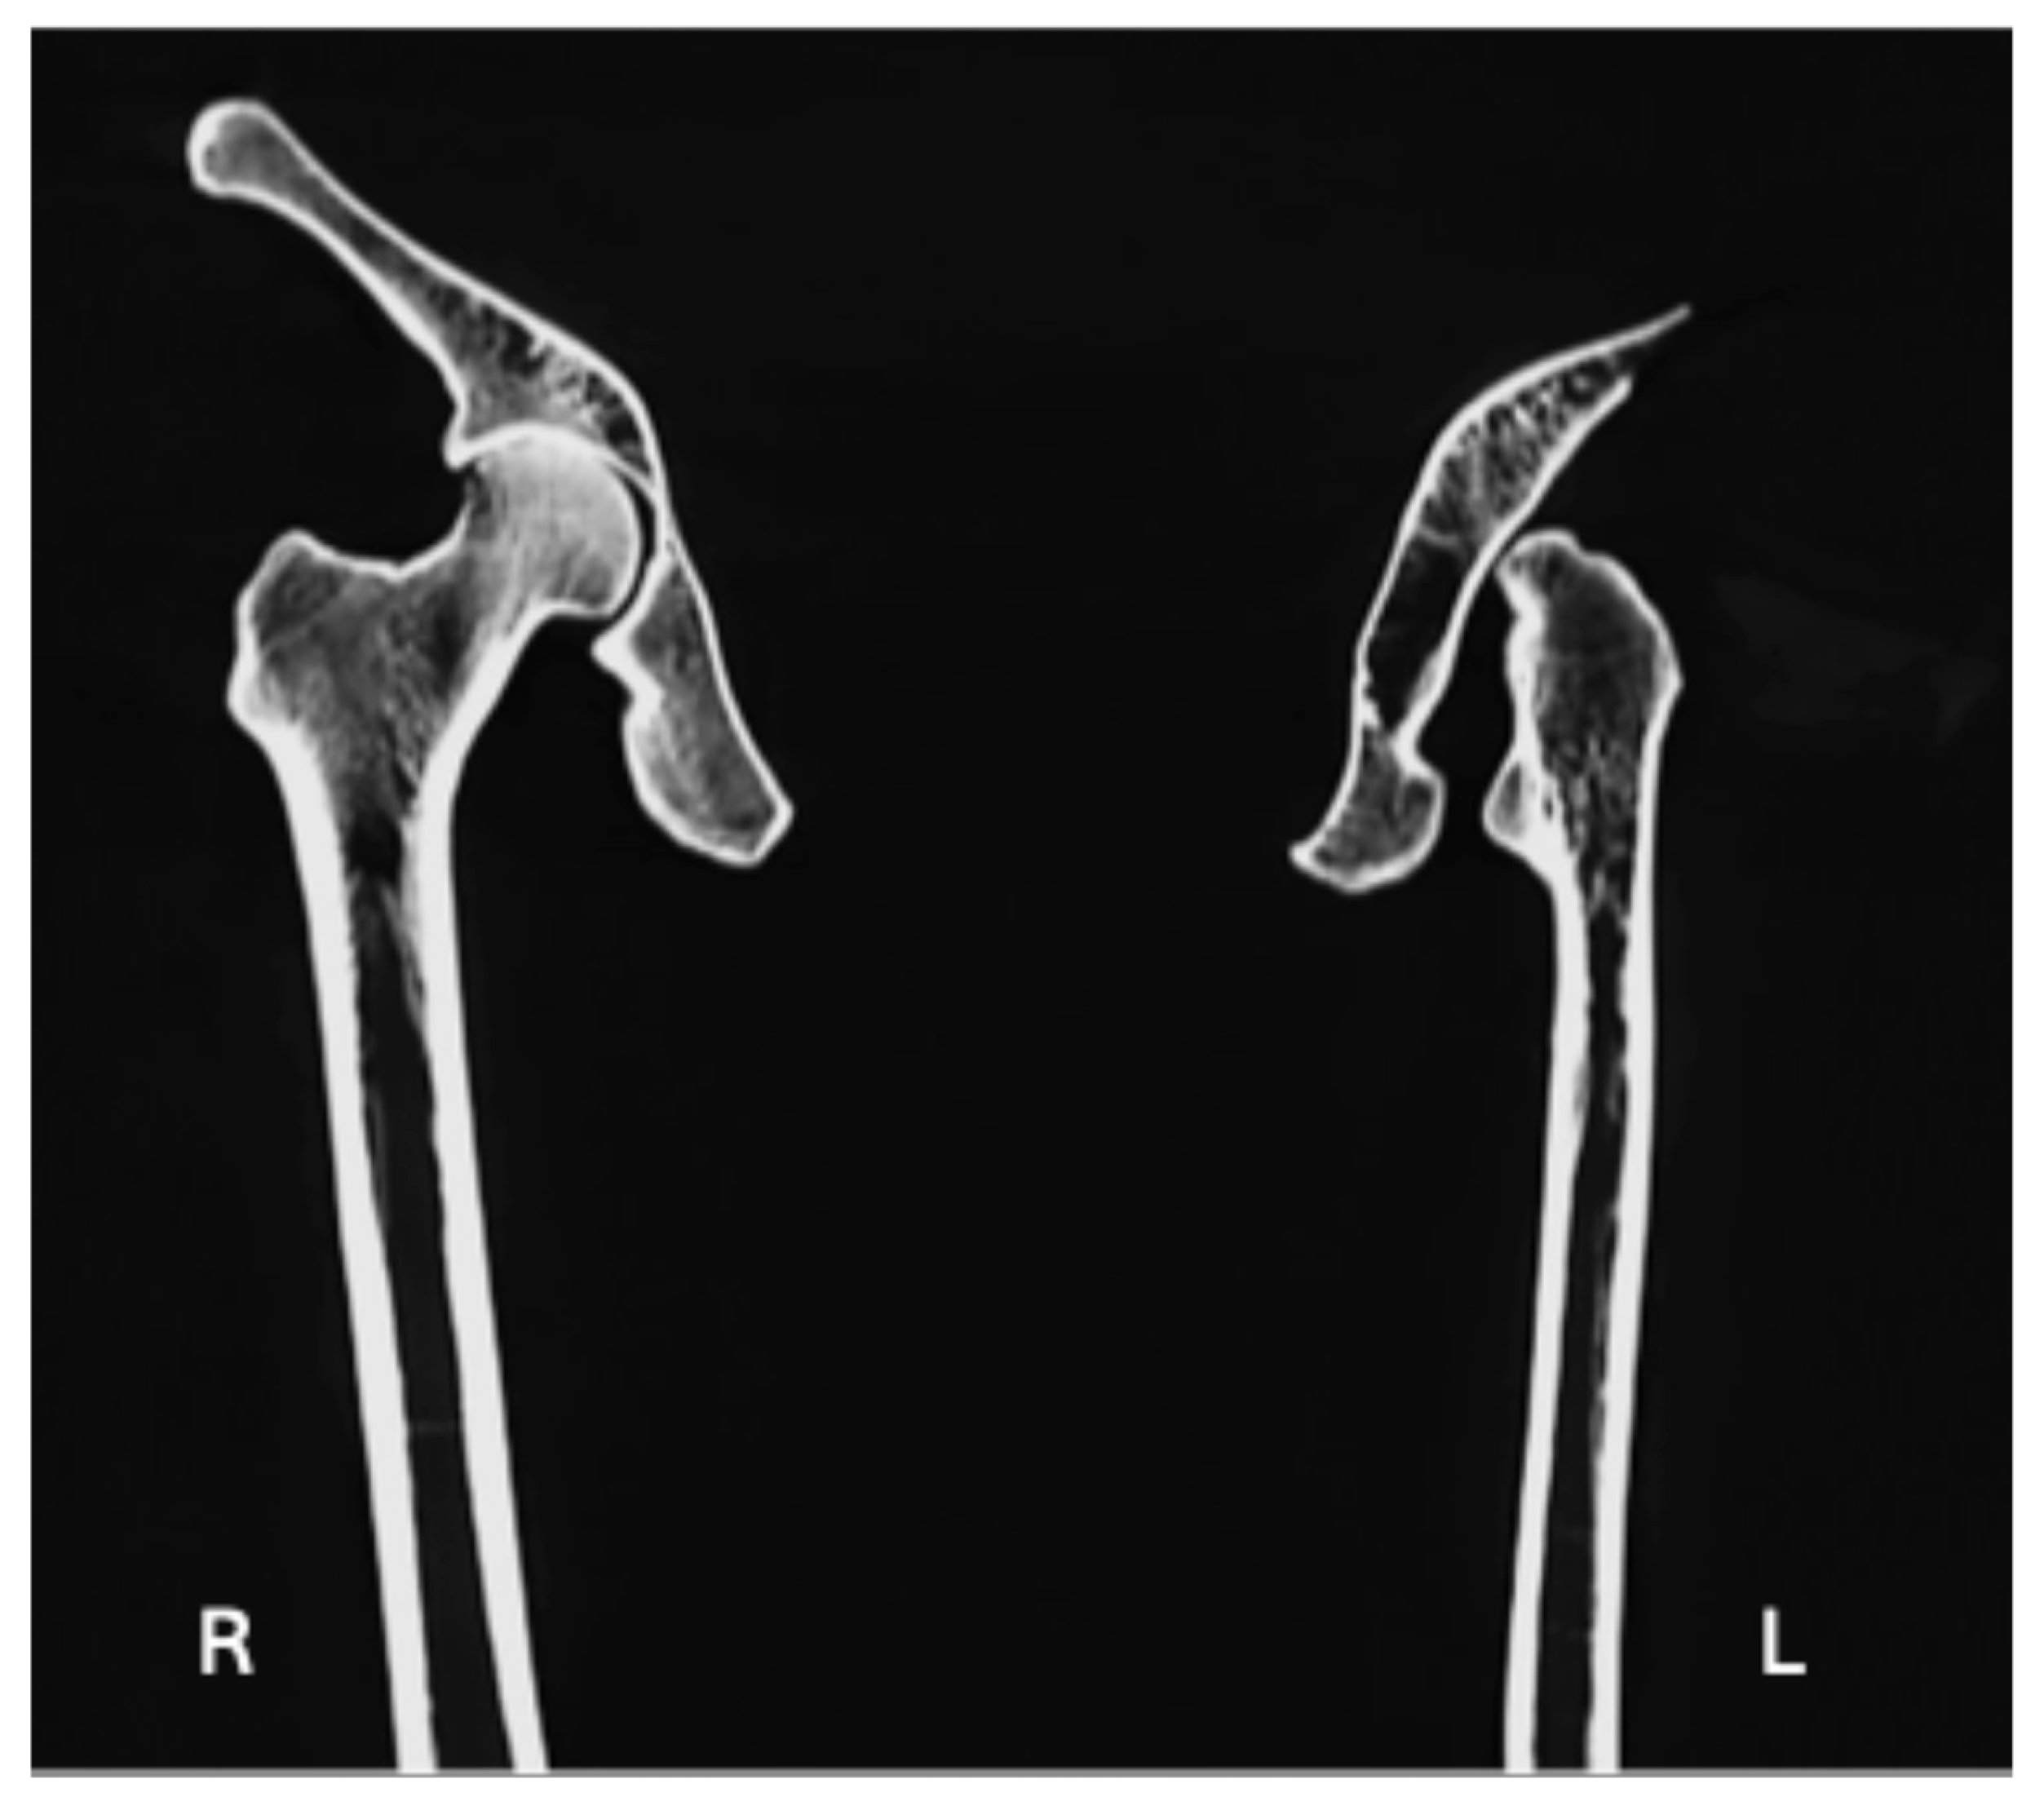

| Hypoplastic/aplastic femoral head (Figure 2b) | X | X |

| Lack of development of the intertrochanteric crest (Figure 2a and Figure 4) | X | X |

| Lack of development of the trochanteric fossa (Figure 2a and Figure 4) | X | X |

| Uppermost origin area for Vastus Lateralis as a flat spike (Figure 2a) | X |

| Triangular: the base facing the obturator foramen and the apex was directed postero-superiorly | Type 1 [32]: smooth shallow depression as articular surface developed just around the AIIS area, which was shifted laterally | Head: hypoplastic/aplastic | Subchondral sclerosis occurring at the knee joint margins |

| Extremely shallow and flatted | Head: Articular facet on the top for an altered joint architecture for the hip bone | Both medial and lateral joint erosion on the tibial plate bilaterally, particular in the left joint. | |

| Change in the posterodistal area, leading to the shifting of the spine of ischium antero-laterally | Trochanteric fossa not developed | ||

| Flat groove for the Obturator Externus | Intertrochanteric crest not fully developed | ||

| Wide acetabular notch | Uppermost attachment area for Vastus Lateralis as a flat spike | ||

| Inverted limbus | Shortening of the bone | ||

| No smooth articulating surface |